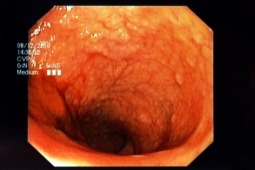

W jednym z ostatnich w 2013 roku wydań czasopisma World Journal of Gastrointestinal Endoscopy ukazała się praca autorów włoskich, którzy dokonali oceny przydatności alternatywnego schematu przygotowania pacjentów do badania kolonoskopowego. Chodzi o zastosowanie roztworu o mniejszej objętości, zawierającego bisakodyl z cytrynianem polietylenoglikolu z dodatkiem simetikonu (PEG-CS).

Autorzy przeprowadzili randomizowane badanie porównawcze, w którym grupą badawczą byli chorzy w wieku 18 – 85 lat, poddawani kolonoskopii diagnostycznej. W jednej z podgrup chorzy otrzymywali bisakodyl wieczorem w przeddzień badania oraz wypijali 2 litry roztworu PEG-CS rano, który pić zaczynali 5 godzin przed badaniem. W drugiej podgrupie pacjenci otrzymywali standardowy czterolitrowy roztwór PEG wg schematu: 2 litry wieczorem w przeddzień badania i 2 litry rano podobnie, jak w grupie otrzymującej PEG-CS. Następnie oceniano jakość przygotowania do kolonoskopii zgodnie z The Ottawa Bowel Preparation Scale (OBPS).

154 chorych uczestniczyło w badaniu: 78 w grupie otrzymującej PEG-CS i 76 w grupie klasycznego roztworu PEG. Wynik w skali OBPS był zbliżony w obu grupach. Odsetek osób skutecznie przygotowanych do kolonoskopii wyniósł 89,7% w grupie PEG-CS i 92,1% w grupie PEG. Wykazano statystycznie lepszą przydatność roztworu PEG-CS, jeśli analizowano jakość uwidocznienia błony śluzowej jelita grubego. Odsetek wykonania pełnych kolonoskopii, a także odsetek wykrytych gruczolaków nie różnił się między obiema grupami. Pacjenci w obu grupach uznali, że sposób przygotowania do badania nie był kłopotliwy, a ponad 90% zadeklarowało, że przy ponownym badaniu zastosowałoby ten sam schemat przygotowania.

Jak więc podsumowują autorzy, przygotowanie do kolonoskopii przeprowadzone rano w dniu badania z zastosowaniem 2 litrów PEG-CS wraz z simetikonem było porównywalnie skuteczne do klasycznego schematu przygotowania do badania.